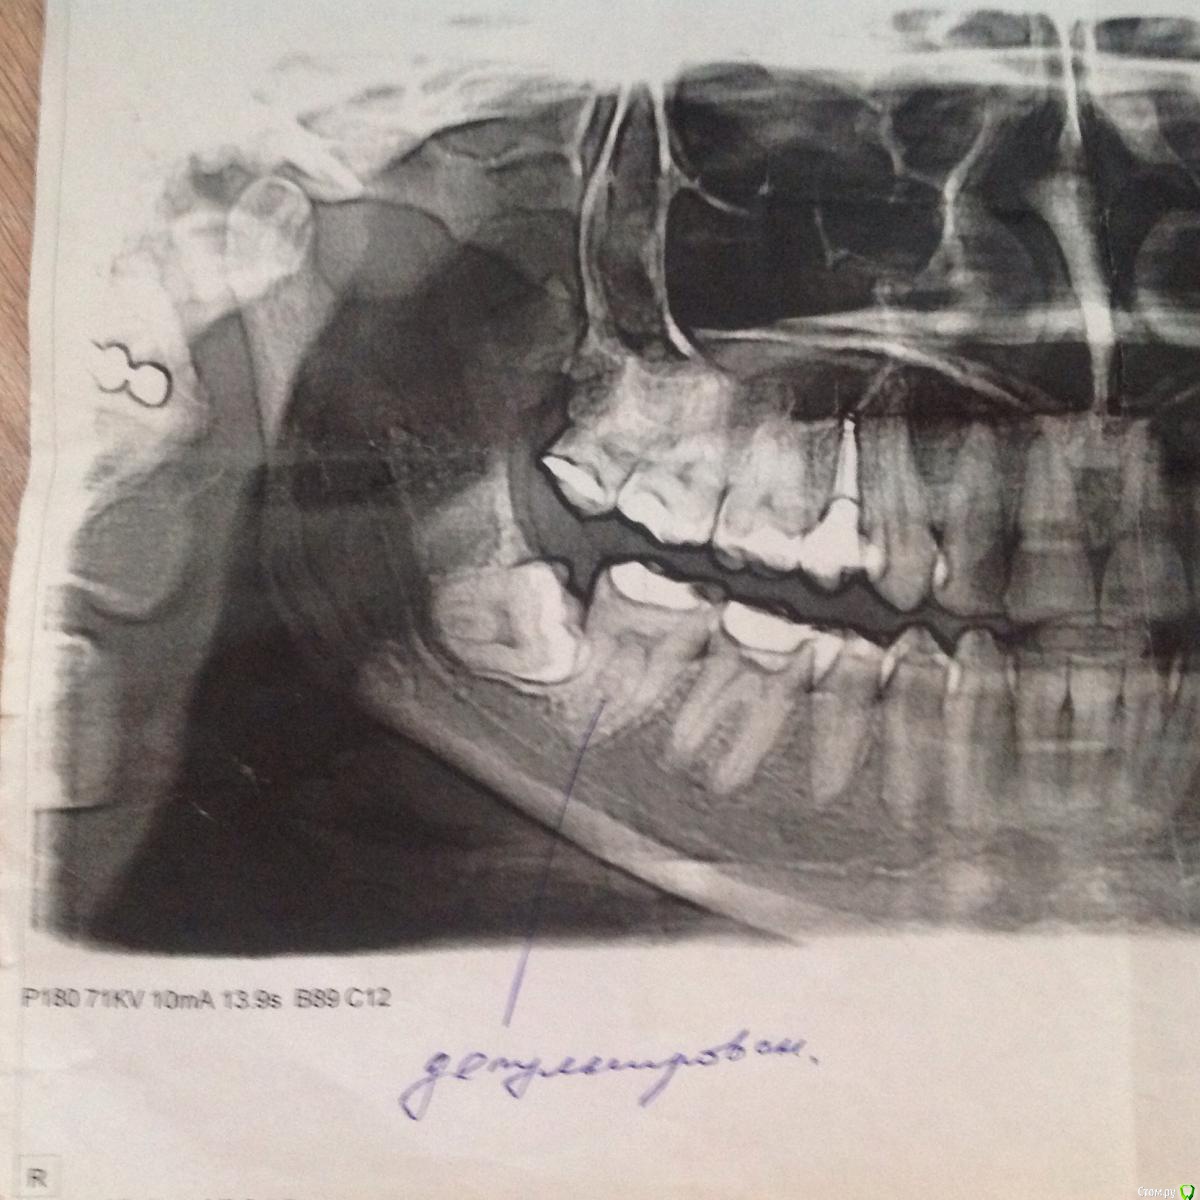

Катруся Опубликовано 30 марта, 2015 Поделиться Опубликовано 30 марта, 2015 (изменено) Добрый!Подскажите, пож-та. У меня болит нижняя семерка правая, депульпированная. Боль ноющая, при надавливании усиливается, на холод/горячее не реагирует. Каналы запломбированы несколько лет назад. Жаловалась в течение этих лет неоднократно своему врачу, но из за зуба мудрости, который лез в семерку, мы думали что болит из за него, т к после депульпирования делали снимок и каналы проверяли на качество заполнения. Зуб мудрости, который на снимке в наст момент удален (4,5 месяца). Снимку тоже 4,5 месяца. Судя по снимку у меня киста... Это я уже сейчас вижу, после того как провела собственное так сказать расследование... Врачи этот снимок видели: и хирург и мой врач-стоматолог... Ничего не сказали.... Подозревать их в некомпетентности у меня нет оснований, т к лечу у них все очень долго и вся моя семья тоже ... Но все же, бывает всякое....Подскажите, каналы запломбированы нормально? Или киста, если это киста, образовалась из за того, что они не до конца заполнены... Или она образовалась из за неверно росшей восьмерки???? Спасибо Изменено 30 марта, 2015 пользователем Катруся Ссылка на комментарий

Катруся Опубликовано 30 марта, 2015 Автор Поделиться Опубликовано 30 марта, 2015 Гарриевич, спасибо за ответ. Прикладываю ОПГ до депульпирования. По моему не профессиональному взгляду там не было такой картины. Про каффердам.... Припоминаю что нет, его я помню лишь последние несколько лет.... Ссылка на комментарий

Катруся Опубликовано 30 марта, 2015 Автор Поделиться Опубликовано 30 марта, 2015 Кстати, нашла этот старый снимок и увидела дату. Значит зуб был депульпирования в мае 2012 года. 3 года получается.... Ссылка на комментарий